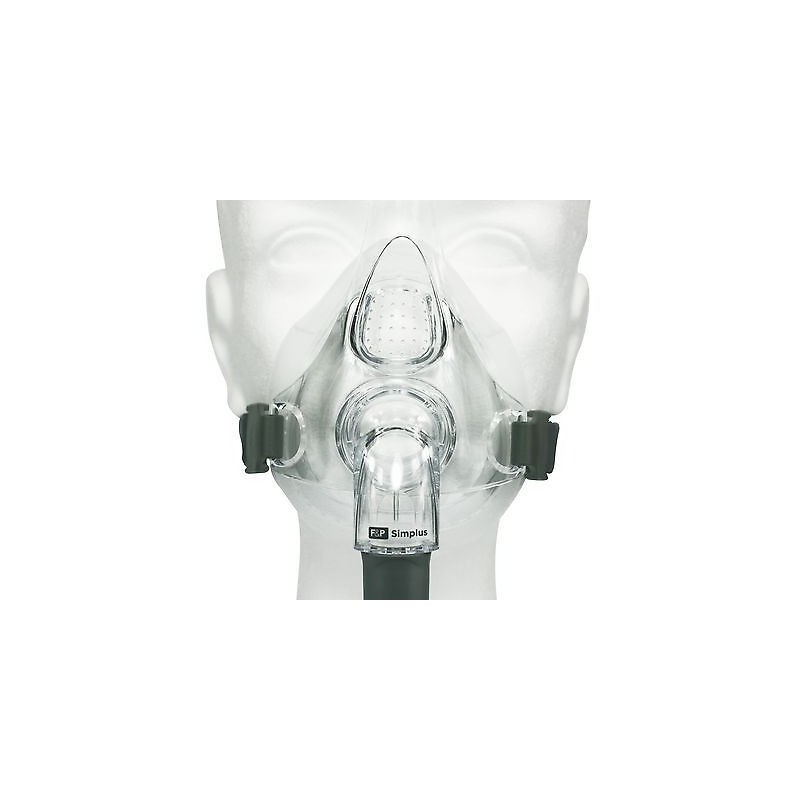

Maschera oronasale per CPAP SIMPLUS

La maschera Simplus è una maschera facciale riutilizzabile ventilata per CPAP e Bi-Level.

E' composta da tre componenti leggeri e anatomici che lavorano insieme per garantire maggiori prestazioni, stabilità e comfort, oltre all’autoregolazione della maschera stessa: cuscinetto in silicone a pezzo unico che “rotola” avanti e indietro sul setto nasale per auto-adattarsi alla conformazione anatomica dell'utilizzatore; fasce nucali a corona facili da usare, da indossare e da regolare, per posizionarsi naturalmente sulla parte alta del capo, consentendo il massimo movimento della testa senza che la maschera si sposti; struttura della maschera dalle linee arrotondate, stabile, resistente e di dimensioni ridotte per consentire un ampio campo visivo.

La maschera e le fasce nucali sono già assemblate in un'unica confezione. Non contiene latex o DEHP.

Maschera oronasale per CPAP SIMPLUS